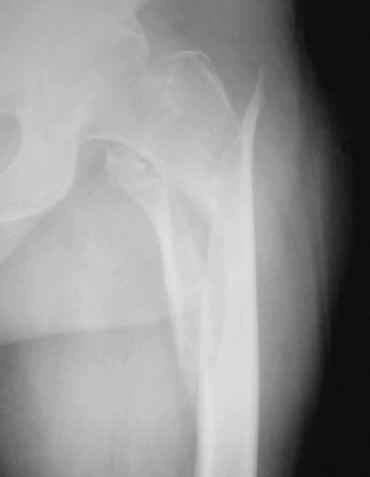

уважаемые коллеги,помогите определиться с тактикой лечения больной:бабушка 72г.с чрезвертельно_подвертельным переломом

и кучей соматических проблем(диабет 2 типа,аг,ревматоидный полиартрит и т.д)находится на скелетном вытяжении.только что стали внедрять у себя блокирующий остеосинтез.какие мнения?